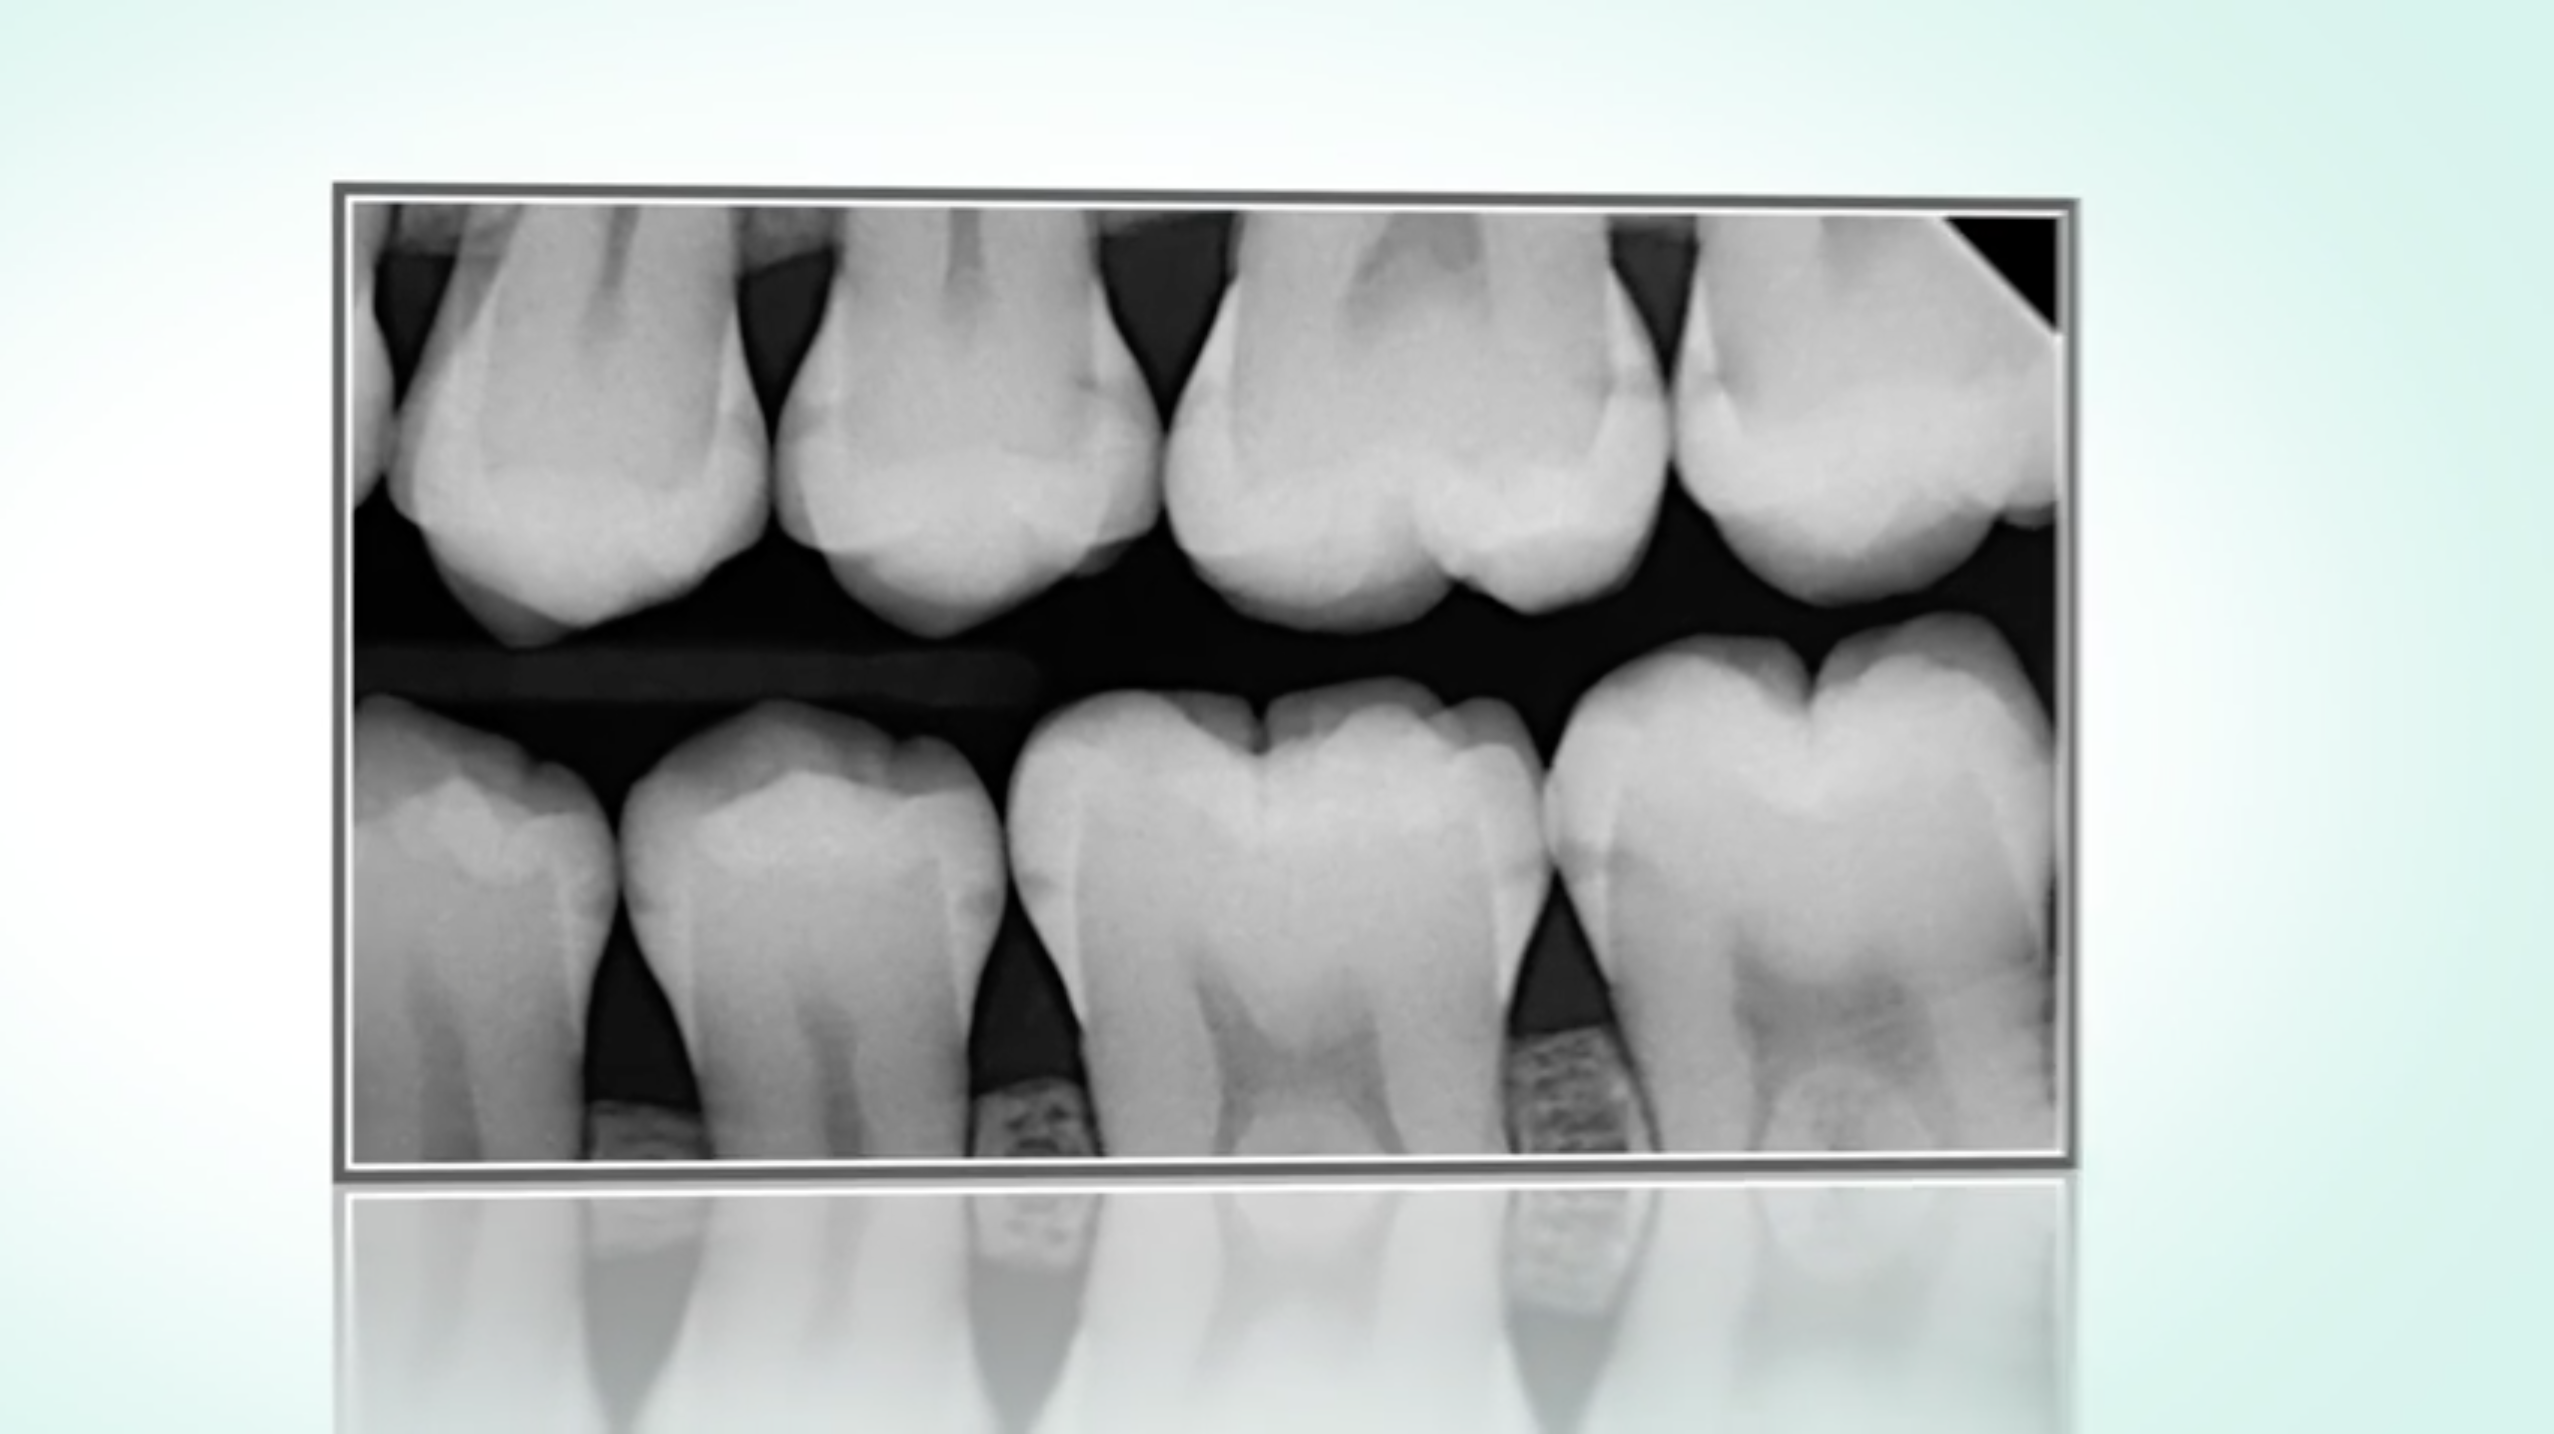

Kariesinfiltration

Die sogenannte Kariesinfiltration bietet eine ganz neue Möglichkeit, beginnende Karies in nur einer Sitzung frühzeitig zu stoppen - ohne Bohren und ohne gesunde Zahnsubstanz zu opfern.

Dies ist allerdings nur bei sehr kleinen, beginnenden Läsionen möglich.

Der »Infiltrant«, ein hochflüssiger Kunststoff, dringt in die poröse Schmelzkaries ein und versiegelt die Diffusionswege für kariogene Säuren. Somit kann die Karies frühzeitig gestoppt werden, im Zahnzwischenraum ebenso wie auf Glattflächen.

Die Kariesinfiltration schließt die Behandlungslücke zwischen Prävention (Fluoridierung und Abwarten) und invasiver restaurativer Therapie.